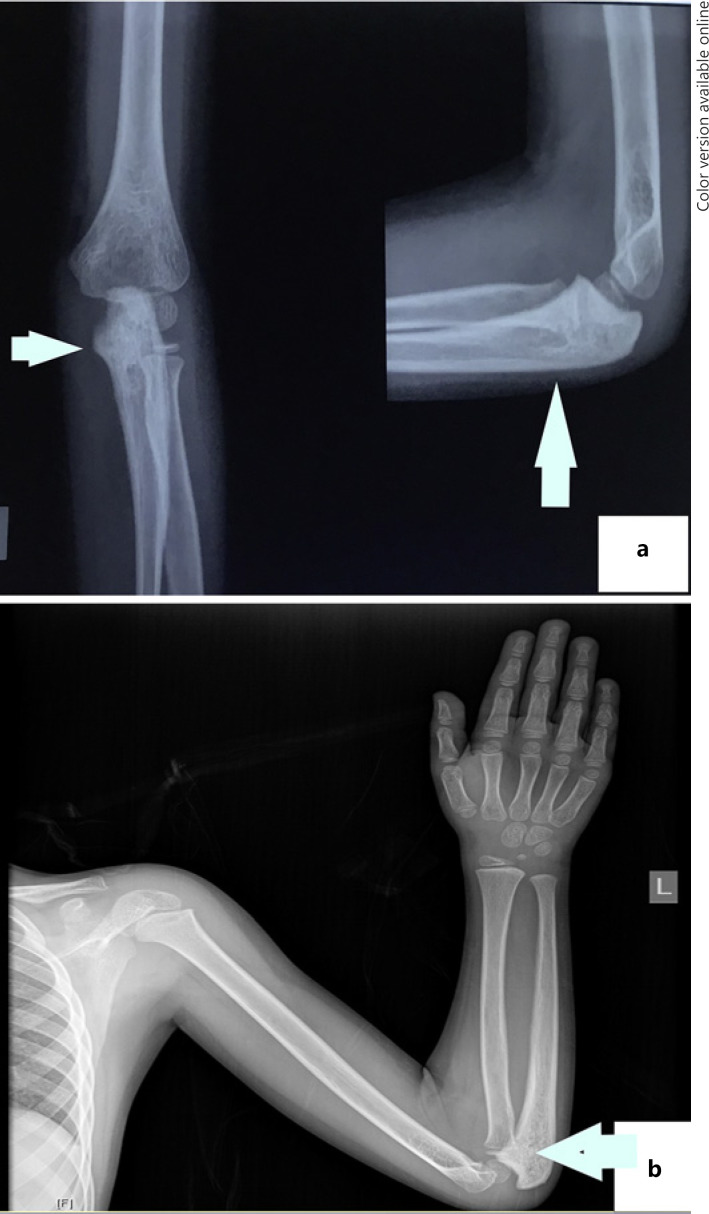

Six and a half years after treatment, the child presented with pain in his left proximal forearm. On examination, there was mild tenderness over the proximal ulnar bone, with no obvious swelling or redness. Radiograph showed lytic sclerotic lesion involving proximal meta-diaphysis of the left ulna with wide zone of transition, solid periosteal reaction, and cortical irregularities (shown in Fig. 1). MRI further confirmed the lesion limited to proximal meta-diaphysis of the left ulna seen as abnormal STIR hyperintensity involving the marrow with cortical erosion and associated soft tissue component (shown in Fig. 2). The bone scan showed uptake only at the left upper forearm. Bone marrow and CSF analysis did not show any evidence of disease. The CT thorax did not show any pulmonary metastasis. Bone biopsy was done, and histopathology showed infiltration of the intertrabecular space by sheets of small round cells having scanty cytoplasm and hyperchromatic nuclei. The differentials considered were small cell osteosarcoma, Ewing's sarcoma, and metastatic small round cell neoplasm. Radiology was not suggestive of osteogenic sarcoma; hence, small-cell osteosarcoma was ruled out. Immunohistochemistry showed tumour cells to be chromogranin cytoplasmic granular positive, synaptophysin diffuse strong positive, CD56 diffuse strong positive, MIC2 cytoplasmic and membrane positive, desmin and myogenin negative (shown in Fig. 3). The tumour cells were positive for synaptophysin, chromogranin, and CD 56, which denotes neuroendocrine/neuroectodermal differentiation. Retinal markers were not done due to non-availability. Ewing's sarcoma translocations done were negative for EWS-FLI1 type 1 and type 2 and EWS-ERG, which together account for 95% of translocations associated with Ewing's sarcoma. Tumour cells in Ewing's sarcoma can be CD56 and synaptophysin positive, but chromogranin negative. Positivity for chromogranin, absence of typical crisp membrane pattern of staining for CD99, and negative translocation ruled out Ewing's sarcoma. Hence, we considered metastatic small round-cell neoplasm in this case. Based on the immunoprofile which showed positive staining for chromogranin, synaptophysin, and CD56, negative RT-PCR for translocations of Ewing's sarcoma, and a positive history of bilateral RB, the possibility of metastatic RB was highly favoured [13].

Fig. 1.

a Pre-chemo X-ray of the left elbow showing mixed lytic sclerotic lesion in the proximal ulna, wide zone of transition involving proximal meta-diaphysis with cortical thickening and irregularity. b Post-chemo showing no evidence of tumour.

The child was started on chemotherapy with vincristine 2 mg/m2 × 1 day, doxorubicin 30 mg/m2 × 1 day, cyclophosphamide 600 gm/m2 × 2 days alternating with cisplatin 100 mg/m2 × 1 day, and etoposide 100 mg/m2 × 5 days every 3 weeks. The child tolerated chemotherapy well with no major complications. After 7 cycles of chemotherapy, the child was re-evaluated. Both eyes showed no active tumour. Repeat X-ray was normal (Fig. 1), and MRI of the left forearm showed residual altered marrow signal intensity involving the proximal meta-diaphyseal region of the left ulna. There was near total regression of the extra-osseous soft tissue when compared to the previous scan (shown in Fig. 2). The child then underwent limb salvage surgery with wide local excision of the ulna at the metastatic site, followed by extracorporeal radiation and reimplantation therapy (ECRT). The bone segment bearing the tumour was resected, the tumour shaved off the bone, and the periosteum stripped. The resected bone segment was covered in an antibiotic soaked gauze, sealed in a sterile plastic, and transported to the radiation unit in a sterile manner where a single fraction of 50 Gy of radiation therapy was given extracorporeally using a 4 MV Elekta Synergy® S linear accelerator. The whole process takes a short time, while the patient continues to be under anaesthesia. The irradiated bone segment was then reimplanted as an auto graft and fixed to the remaining ulna with a 15-hole recon plate. The elbow capsule, the medial and the lateral ligaments were then reattached. Triceps tendon was also reattached. The post-operative period was uneventful. The histopathology of bone scrapings sent from the surgical margins did not show any viable tumour. After the surgery, the child received one more course of chemotherapy with vincristine, doxorubicin, and cyclophosphamide. The patient is now 1 year 11 months from the diagnosis of the ulnar lesion and remains recurrence-free. Repeat X-ray showed completely reunited bone. The child has a good range of movements and normal elbow function.